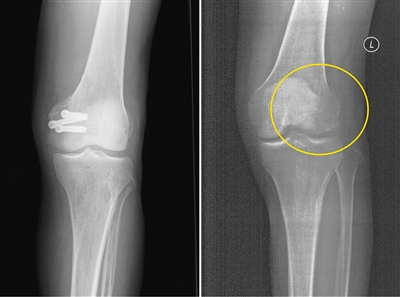

今年5月,患者張強(化名)不慎扭傷,造成左股骨遠端骨折。由於骨折部位靠近關節面,使用金屬螺釘固定時應力過大,會影響骨折癒合;1年後還需要手術將金屬螺釘取出,可能造成二次創傷。患者入院之後,團隊經過詳細探討病情、細緻閲片後認為,該患者符合可降解蠶絲螺釘固定的適應證。術中團隊對該患者使用可降解蠶絲螺釘固定骨折塊,術後的CT片中沒有任何偽影,可以清晰地看到骨折塊已經完全復位,並且解除了患者二次手術取出螺釘的負擔和困擾。